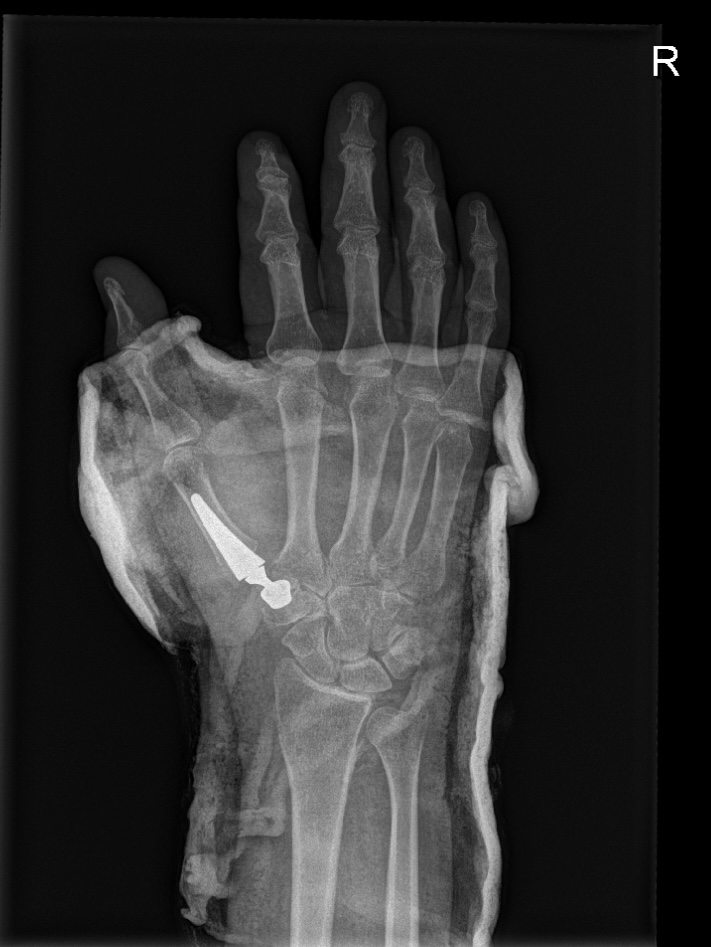

Ja inderdaad. Alvorens ik de patiënt bevestig dat hij of zij baat heeft bij een duimprothese laat ik evenwel eerst nog een scan nemen om enkele medisch/technische zaken na te kijken. Zo wil ik weten of het überhaupt mogelijk is om een prothese te plaatsen en of er in de pols ook geen andere oorzaken zijn van de pijn aan de hand.

De ingreep gebeurt in dagziekenhuis. De patiënt hoeft dus niet te overnachten en kan de dag zelf naar huis. Tijdens de ingreep wordt via een 4-tal centimeter lange incisie toegang gemaakt tot het versleten gewrichtje. Aan beide kanten van het gewricht wordt het afgesleten kraakbeen verwijderd. In het middenhandsbeentje van de duim wordt een steeltje geplaatst dat ter hoogte van het gewricht eindigt in een bolletje. Dat bolletje zal dan contact maken en draaien in een pannetje dat wordt bevestigd aan de andere kant van het gewricht. De ingreep zelf duurt ongeveer een 40 minuten. Na de ingreep krijgt de patiënt een immobilisatie van de duim tot de controleafspraak. Vanaf dan mag de duim weer nat gemaakt worden en is het aangewezen om de duim langzaamaan opnieuw te gebruiken.